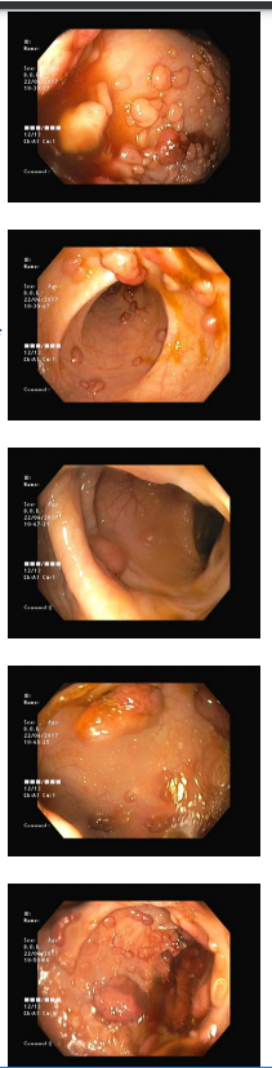

20 year old presented to the gastroenterology department with complain...

Read More